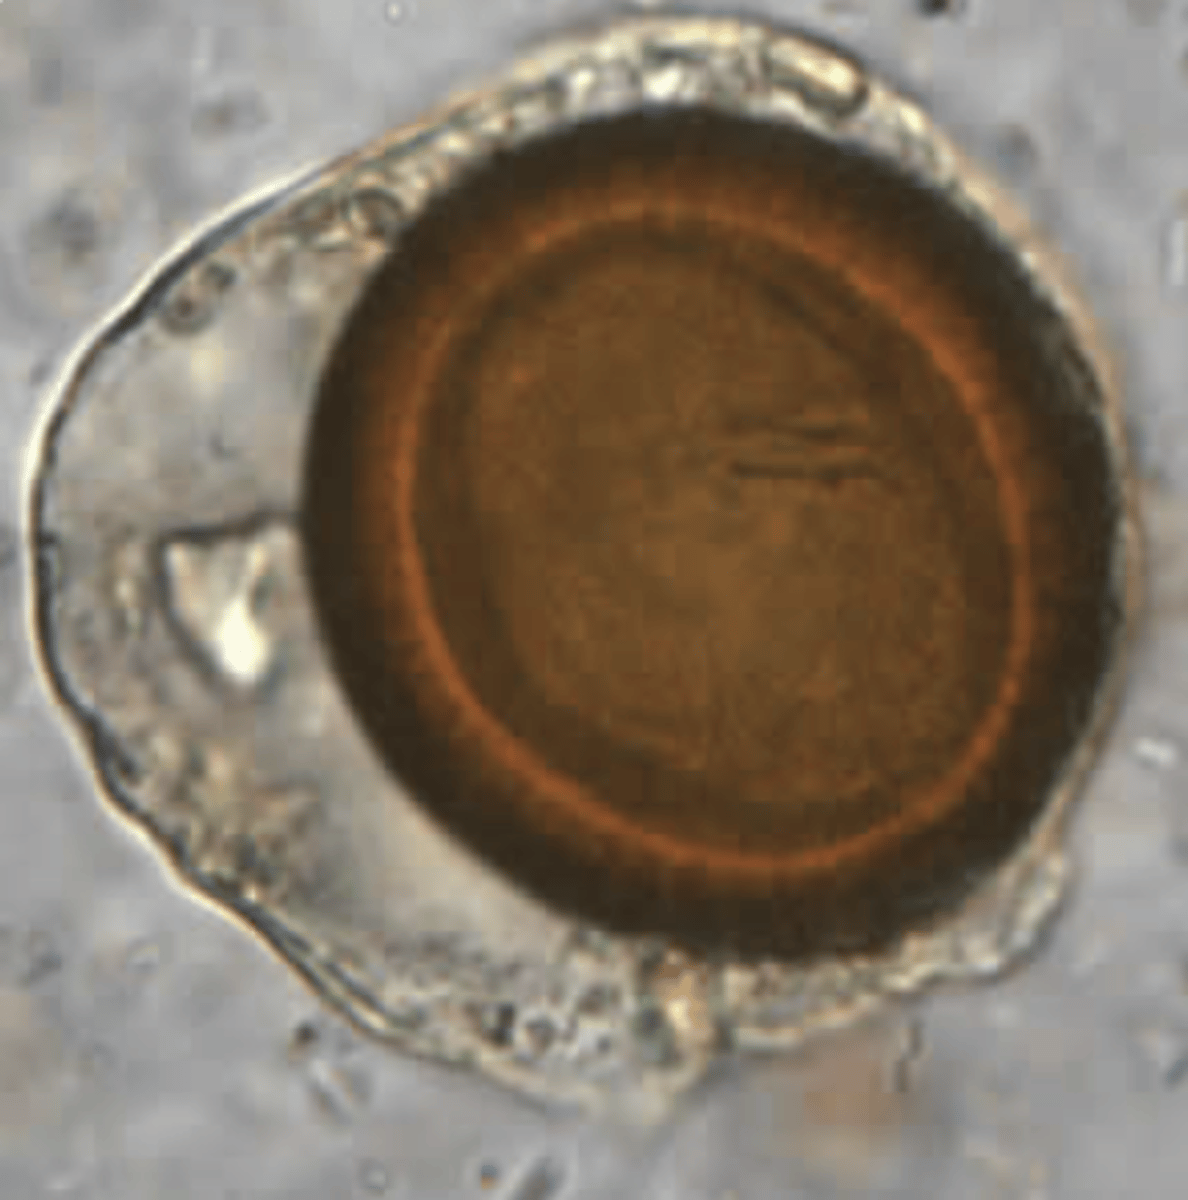

Dibothriocephalus latus (Diphyllobotrium latum)